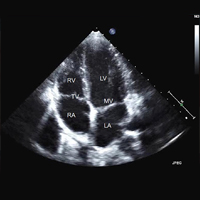

Cilj programa je: Upoznavanje sa infektivnim endokarditisom (IE), ozbiljnim oboljenjem sa visokim mortalitetom uprkos velikom napretku u dijagnostici i lečenju. Usvajanje znanja o tome kada treba posumnjati na IE i koje dijagnostičke procedure treba primeniti. Osposobljavanje za postavljanje dijagnoze IE.

Cilj programa je: Upoznavanje sa metodama dijagnostike infarkta miokarda. Sticanje znanja o karakteristikama dobutamin stres eho testa i njegovoj primeni. Razumevanje uloge medicinske sestre u pripremi bolesnika i izvođenju dobutamin stres eho testa.

Cilj programa je: Pojmom „akutnog koronarnog sindroma“ (AКS). Značajem biomarkera u dijagnozi i lečenju bolesnika sa AКS. Značajem biomarkera u dijagnozi srčane insuficijencije. Značajem markera nekroze miocita u dijagnozi akutnog infarkta miokarda. Markerima inflamacije u akutnom koronarnom sindromu. Markerima srčane funkcije.